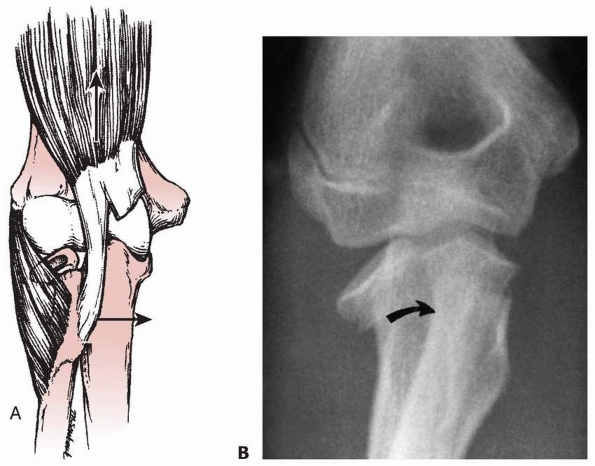

three types based on the location of the fracture line (Fig. 11-7).

Fractures associated with an elbow dislocation are subdivided into two

types. The first is based on the original concept proposed by Jeffrey42 that the fracture occurs during spontaneous reduction (Fig. 11-8A). In this case, the radial head lies proximal to the posterior aspect of the joint. The second is based on Newman’s70

concept that the fracture and displacement occur during the process of

dislocation of the elbow. In this type, the radial head lies distal to

the anterior portion of the joint (see Fig. 11-8B).

FIGURE 11-8 Dislocation fracture patterns. A.

Type D: The radial neck is fractured during the process of reduction by the capitellum pressing against the distal lip of the radial head.125 B. Type E: The radial neck is fractured during the process of dislocation by the capitellum pressing against the proximal lip of the radial head.98 C. Radiographs of a radial head that was fractured during the reduction of the dislocation (type D). The radial head (solid arrow) lies posterior to the distal humerus, and the distal portion of the neck (open arrow) is anterior. (Courtesy of Richard E. King, MD.) D. Radiograph of the dislocated elbow in which the fracture of the radial neck occurred during the process of dislocation (type E). |